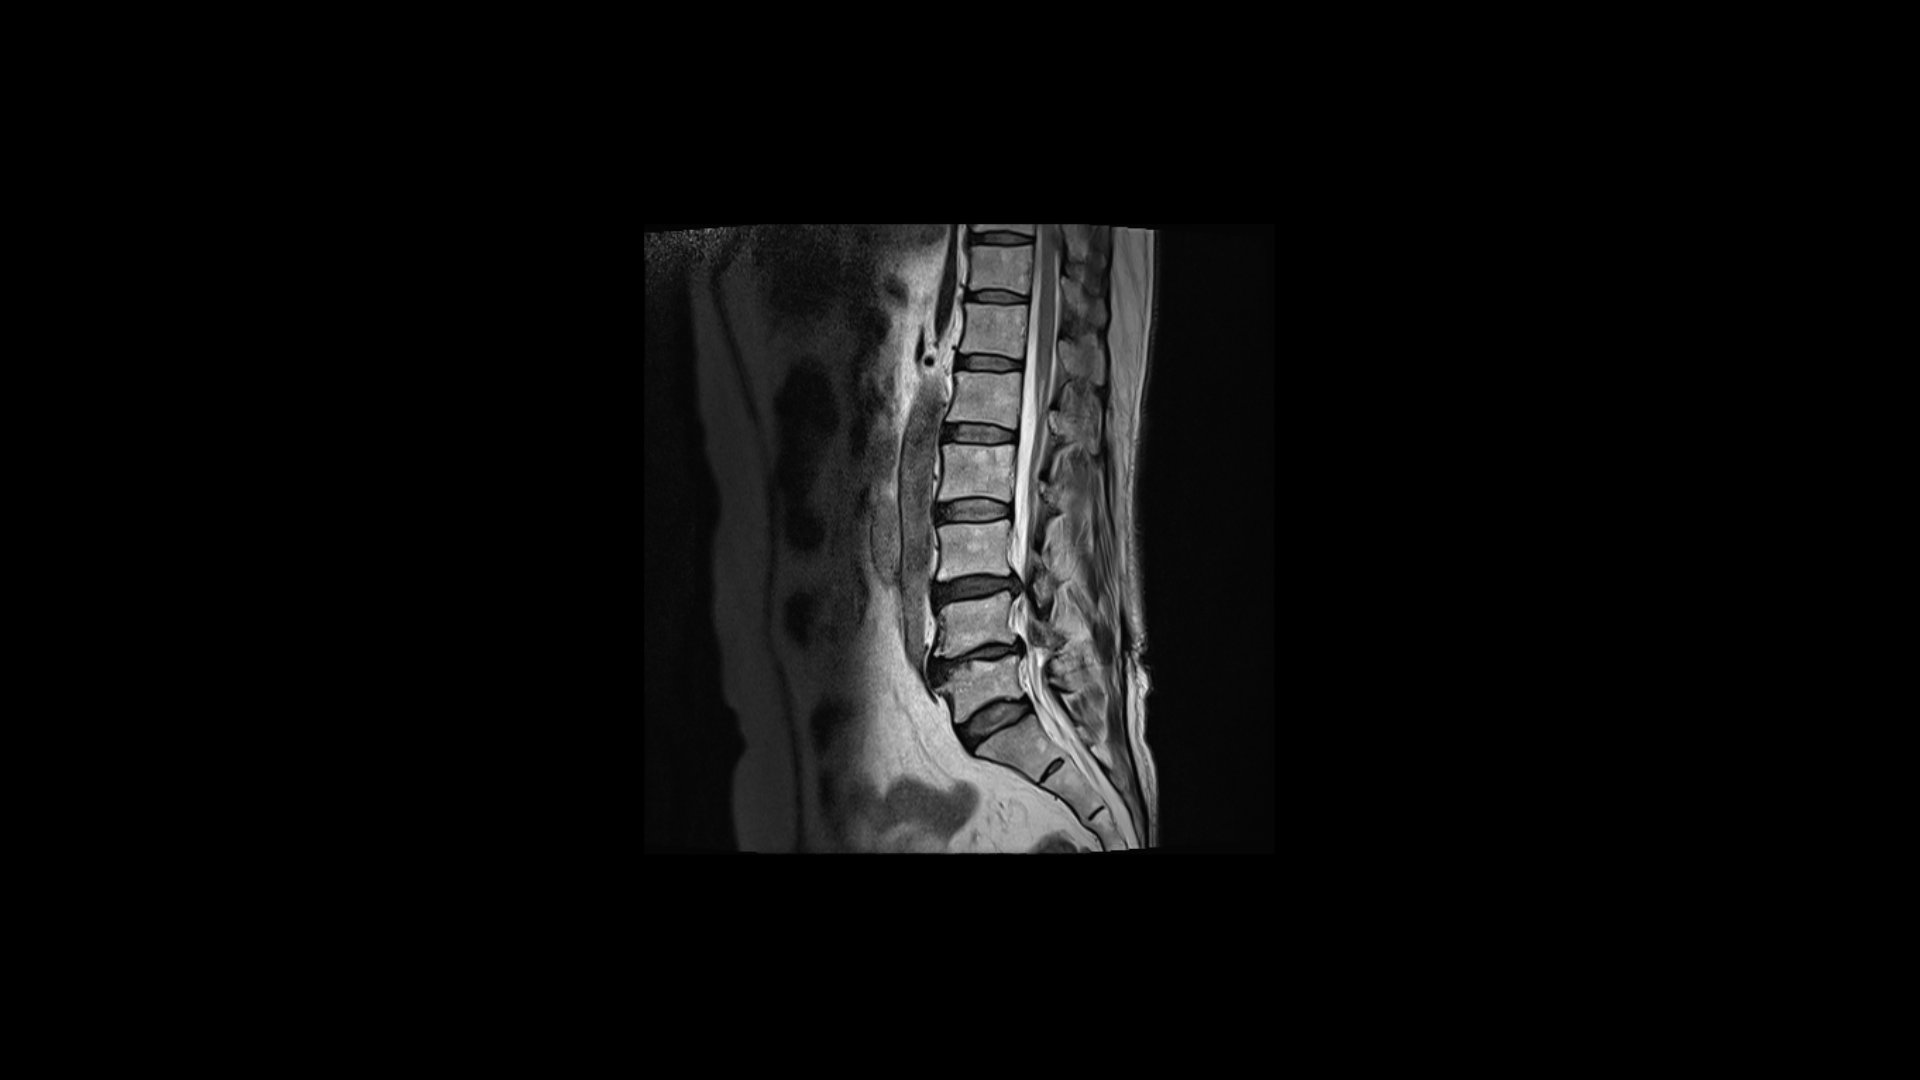

허리MRI를 보면 두 마디의 퇴행성디스크와 추간공협착이 있습니다.

3번 4번은 왼쪽 중앙으로 밀려나와있고

4번 5번은 왼쪽 신경이 빠져나가는 추간공이 뼈가 자라면서 좁아져 추간공협착이 있습니다.

또 왼쪽 후궁에는 과거에 받은 수술의 흔적도 보입니다.